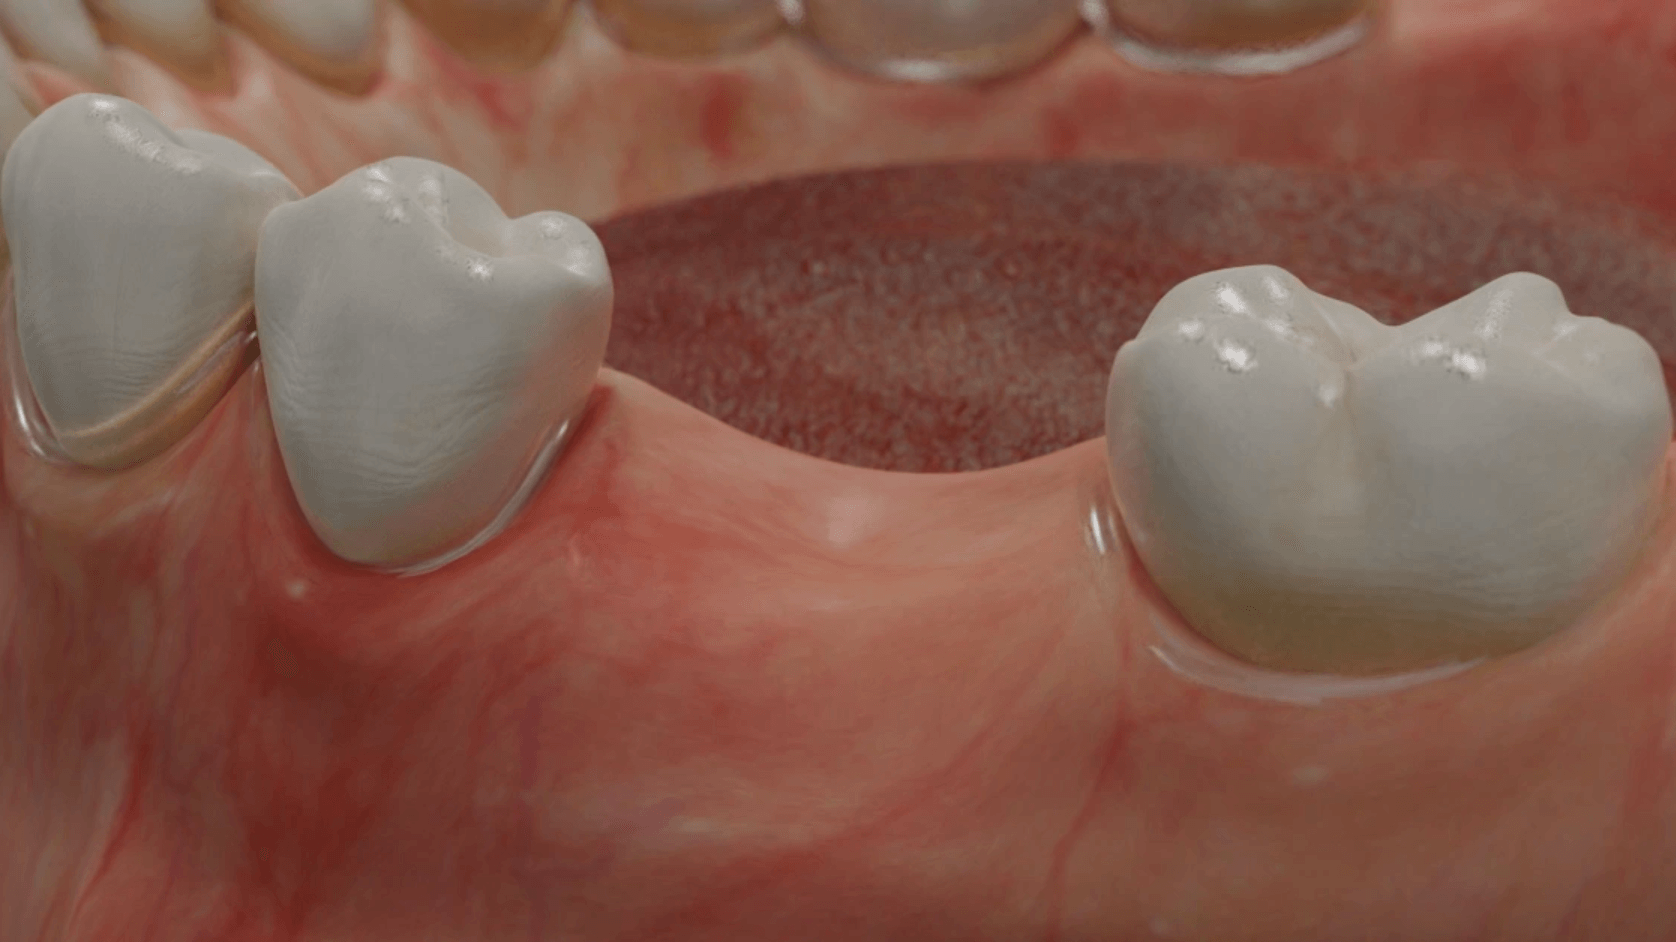

Durch den Verlust des Zahnes wandelt sich der Kieferknochen um. Nach der oberflächlichen Heilung wird das knöcherne Zahnfach vom Körper rasch abgebaut. Knochen ist für den Körper ein "teures" Gewebe, und ohne die funktionelle Kaubelastung durch einen Zahn gibt es für den Körper keinen Grund mehr, das knöcherne Zahnfach zu erhalten. Allein im ersten Jahr nach der Zahnentfernung gehen 50% des umgebenden Knochens verloren! Das ist insbesondere dann von Nachteil, wenn geplant ist, später ein Implantat für den Ersatz des Zahnes zu setzen. Ohne kiefererhaltende Maßnahmen reicht oftmals der nach der Heilung verbliebene Knochen nicht mehr aus, ein hinreichend großes Implantat einzusetzen bzw. dieses auch ideal zu positionieren.

Aus diesem Grund werden seit vielen Jahren

Knochenersatzmaterialien aus tierischem, pflanzlichen oder mineralischen Ursprung verwendet, um die Schrumpfung des Kieferknochens aufzuhalten und dadurch die ursprünglichen Dimensionen zu bewahren.